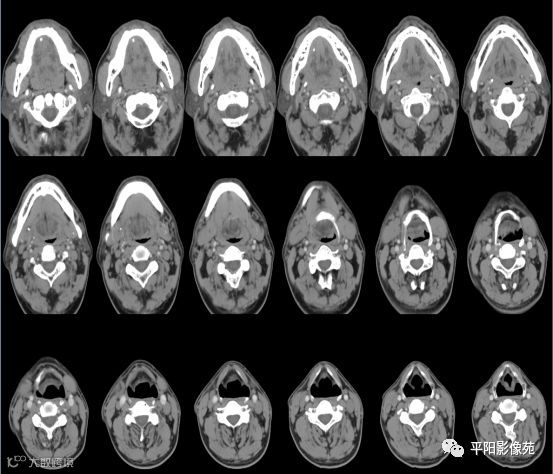

双侧颌下腺、腮腺对称,形态完整,右侧颌下腺强化程度较左侧略低,其内涎腺管增粗,周围脂肪间隙清晰,邻近骨质未见异常,右侧涎腺走行区可见结节样致密影,较大者大小约0.5cm,双侧颌下软组织对称,未见异常密度,所扫范围颈部未见明显肿大淋巴结。

考虑右侧涎腺管结石。

右侧颌下腺强化程度较左侧略低,涎腺管扩张,考虑炎性改变,请结合临床。